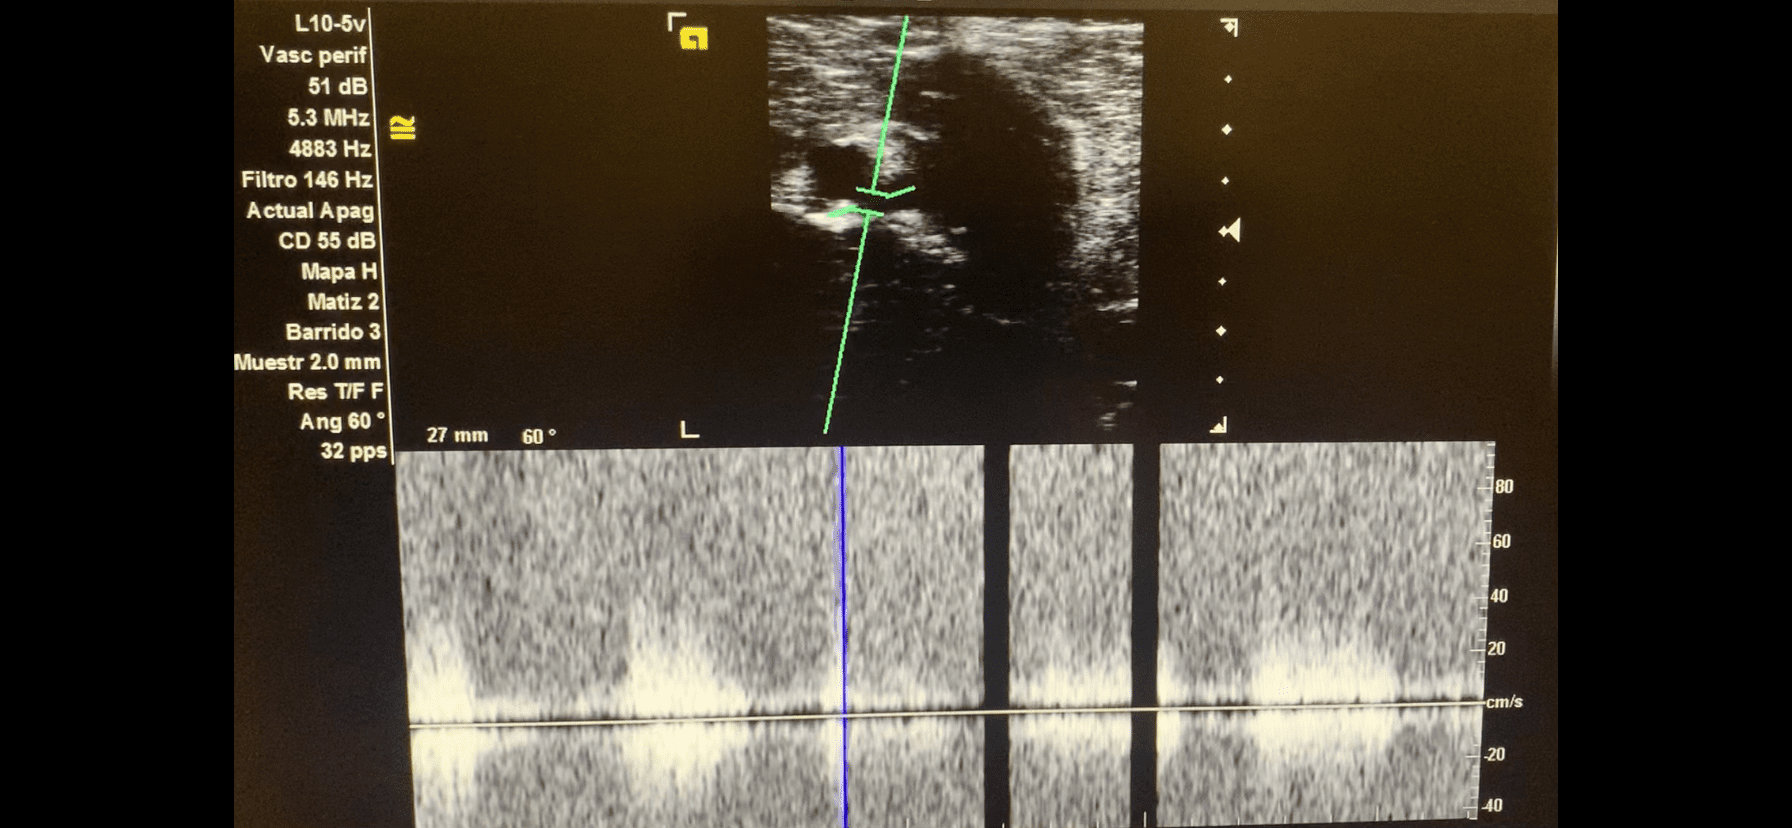

Imagen 3. Tono pulsátil de la fistula arteriovenosa.

AngioTC miembro inferior derecho: arterias femoral común, profunda y superficial permeables, de calibre normal, sin estenosis. Gran fístula arterio-venosa en tercio medio de femoral superficial, de alto flujo.